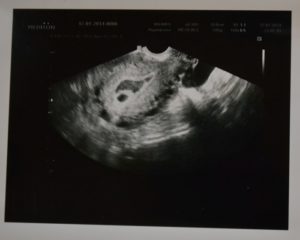

Что видно на фото УЗИ на 6 неделе беременности?

Получив на руки заветную фотографию будущего малыша, не стоит пытаться разглядеть на ней на кого похож ребенок – это невозможно.

Если внимательно посмотреть на фото, то удастся заметить два небольших пятнышка, одно из них – желточный мешочек, второе – ваш малыш.

Фото плода

В общем, пока ничего значительного будущие родители на фотографии не увидят, поскольку малыш еще слишком мал. Но в этом есть своя прелесть – поскольку все приятные моменты еще впереди.